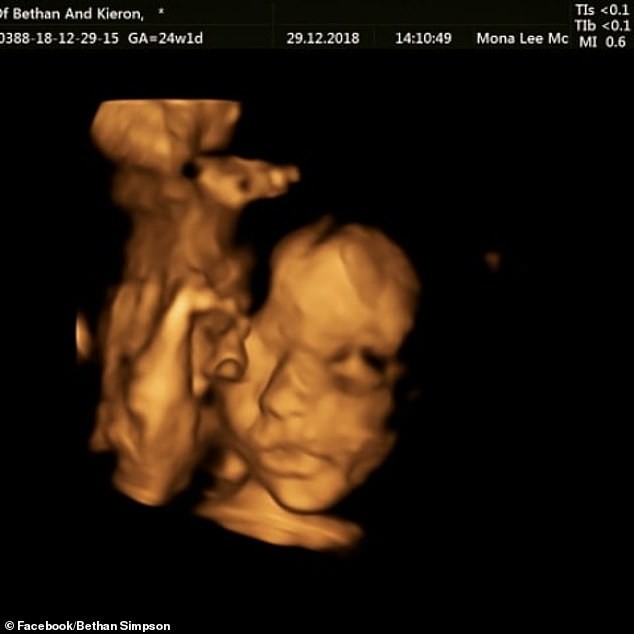

喺懷孕24週後,Bethan接受胎兒手術。手術期間,醫生會先打開子宮,用特定器材將所有血管鉗制,確保膜組織被肌肉固定。之後會用超聲波揾出胎盤同胎兒嘅位置,觀察BB背部後,將脊髓放回椎管,整個過程BB都會留喺子宮入面,最後醫生會將切口縫合,令媽媽繼續懷孕,直至BB出世。

Bethan手術十分成功,成為英國首位成功接受胎兒手術嘅媽媽,醫生預計BB會喺4月出世,Bethan指自己從未後悔接受手術,因為「雖然胎兒手術喺以前或會存在好大風險,但宜家科技進步好多,我哋都要相信,而且絕對唔可以由自己判BB死刑」。手術後,Bethan指「BB每日都踢我,依種感覺手術後都未變過!」